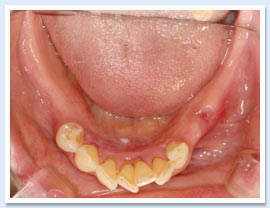

歯周治療後に多くの歯が残せれば固定式のブリッジなどで治療を終えることができますが、少ない本数しか残せなかった場合は可徹性義歯(いわゆる入れ歯)が必要になってきます。その最たるものは部分入れ歯ですが、歯周病に罹患した歯でも定期的なメインテナンスを受けることで長期間入れ歯の支台として機能することが可能になります。(※義歯は上下ともに保険診療の義歯ではありません)

慢性辺縁性歯周炎の治療(11年経過)です。歯周基本治療のみの治療です